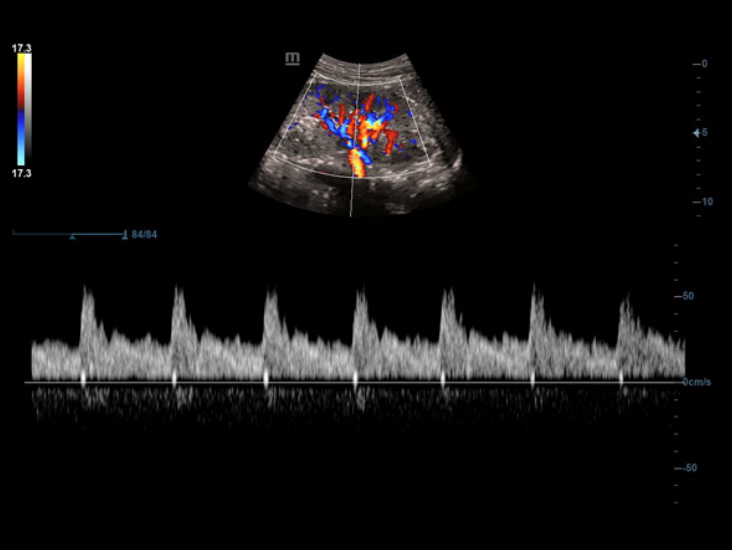

Ak?ll? Takip, yaln?zca tek dokunu?la ?al??arak, vaskÞler g?rÞntÞleme i?in h?zl? ve ak?ll? optimizasyon sa?lar. Otomatik takiple, Renk, GÞ? ve PW spektrumunu optimize edebilir ve zaman alan ad?mlar? azaltabilir. Bu nedenle, vaskÞler muayene i? ak??? optimum g?rÞnÞmle basitle?tirilir.